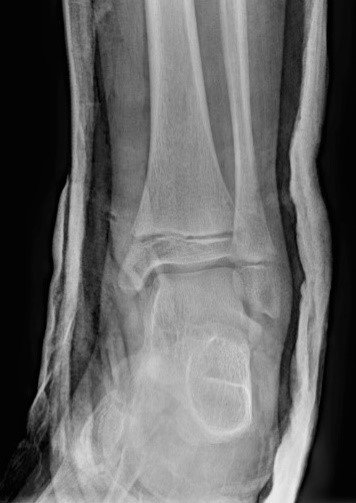

Загальна рентгенографія